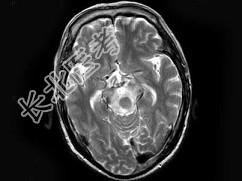

- 单项选择题男,70岁, 头痛,嗜睡伴癫痫发作2次, 行MRI平扫及增强扫描见颅内多发病灶,曾行放射治疗, 病灶明显缩小(此图为治疗前图),据此最可能的诊断为 ( )

A、颅内转移瘤

B、淋巴瘤

C、胶质瘤

D、血管瘤

E、未见异常